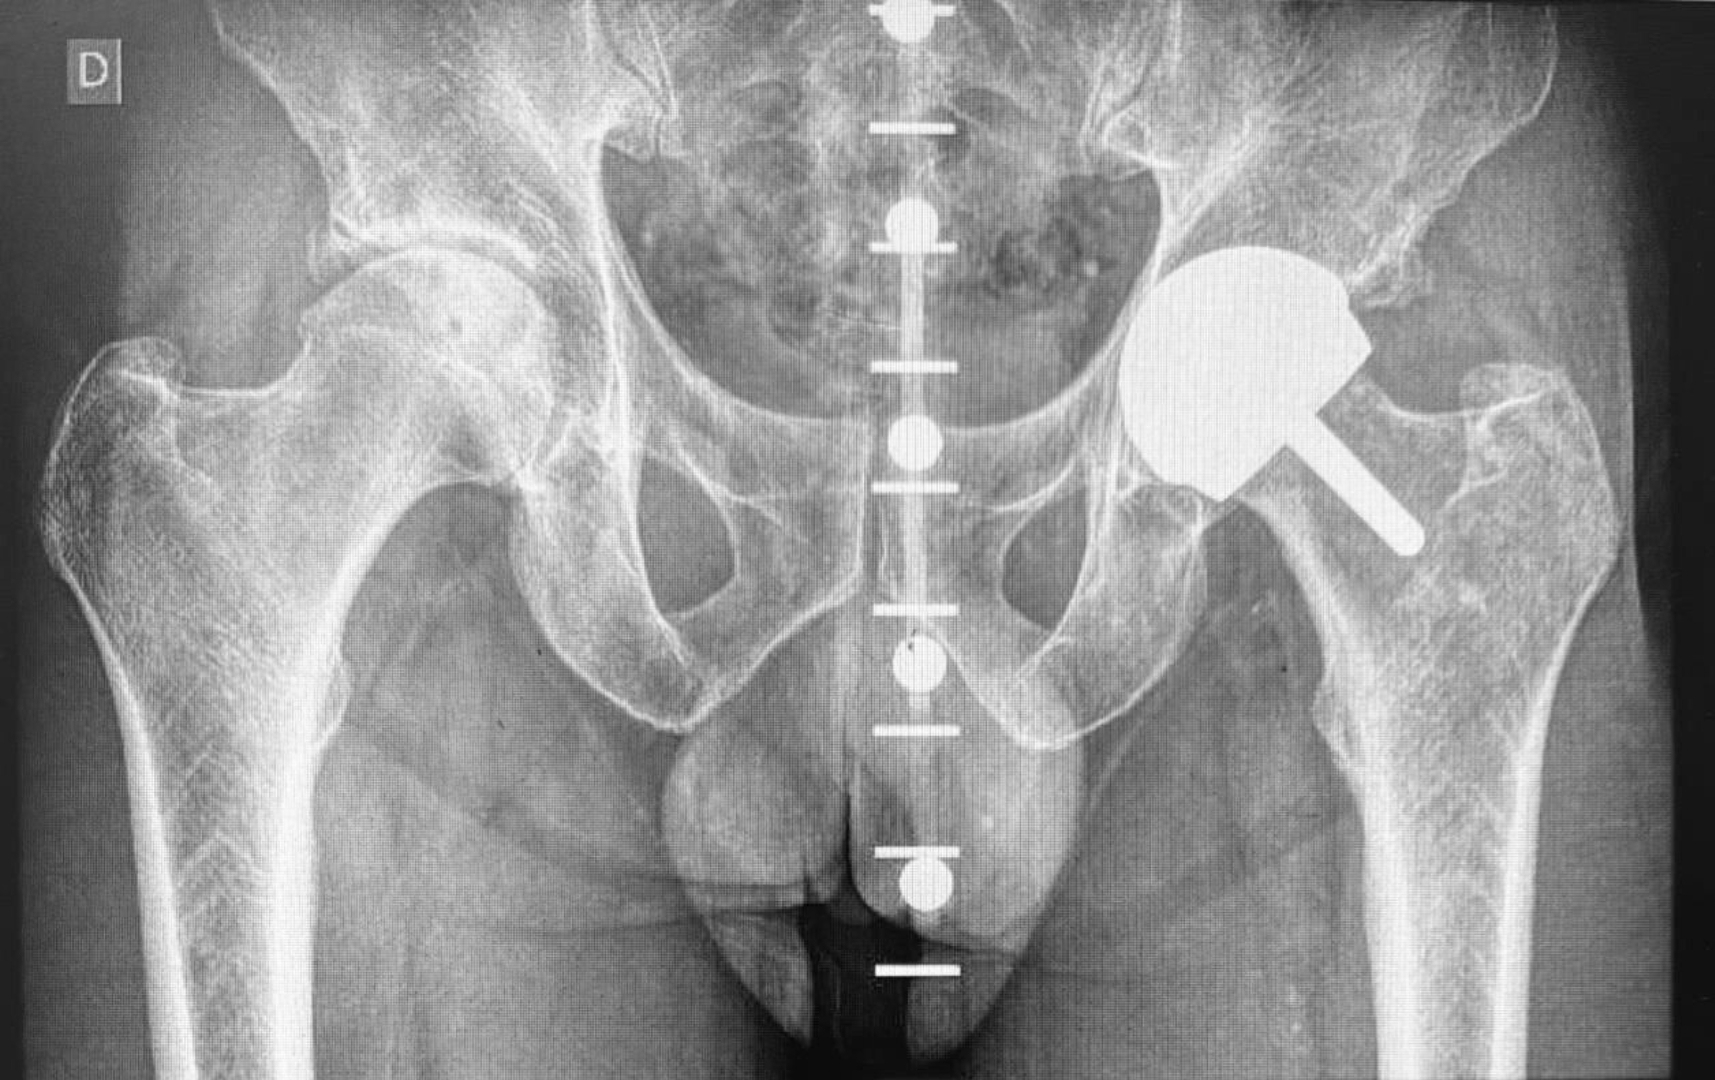

El servicio de Traumatología y Cirugía Ortopédica del Hospital Quirónsalud Sagrado Corazón ha incorporado un software de reconstrucción tridimensional para la colocación más precisa de prótesis de cadera. Esta novedosa técnica de planificación quirúrgica protésica está especialmente diseñada para pacientes jóvenes, activos y que desean volver a realizar actividad deportiva con regularidad. En concreto, el software, diseñado y desarrollado a petición del equipo de Traumatología y Cirugía Ortopédica del hospital, se está aplicando en las cirugías de prótesis de superficie de cadera, las cuales exigen una alta precisión a la hora de colocar todos los componentes en su posición adecuada, ya que no se corta el cuello del fémur, sino que se recubre la cabeza femoral. Este tipo de implantes reducen el riesgo de luxación y, además, permite respetar el hueso casi íntegro en caso de tener que hacer un recambio. Es por ello que la aplicación de la planificación usando modelos 3D tiene una especial incidencia en estos procesos y, en concreto, en la colocación de este tipo de prótesis por su particularidad quirúrgica, según destaca el doctor Daniel Cansino, Jefe de Servicio de Traumatología y Cirugía Ortopédica del Hospital Quirónsalud Sagrado Corazón. “Nos valemos de la impresión en tres dimensiones para poder realizar un modelo que nos sirva para poder colocar el componente femoral en la posición adecuada, dando como resultado una mejor función articular y un menor desgaste en el futuro de este modelo protésico”, añade el doctor Cansino. Además, entre todas sus ventajas, la aplicación de esta tecnología en estos procesos reduce el tiempo de exposición de la cadera, es decir, se acorta el tiempo de la intervención, reduciendo, por tanto, el riesgo de infección y cualquier otra complicación perioperatoria. El doctor Cansino apunta que este software se puede utilizar también para realizar plantillas de corte para poner prótesis de rodilla, para realizar diferentes procedimientos de osteotomías, donde se tienen que hacer algunos cortes en determinados huesos, o para realizar procedimientos de alineación del eje de carga de la pierna en pacientes jóvenes que está teniendo inicio de artrosis, a los cuales se les someten a estas técnicas correctoras con el propósito de retrasar la aparición de esta patología o para evitar la temprana colocación de prótesis de rodilla. Esta forma de implantación de la prótesis usando modelos diseñados en guías que se han hecho bajo impresión tridimensional, es un modelo que se está implementando en Quirónsalud Sagrado Corazón con el objetivo de estandarizarlo. “El uso de estas tecnologías, y en concreto en el caso de las prótesis de superficie de cadera, va a facilitar que nuevos cirujanos que estén iniciándose en este tipo de cirugías puedan hacerla con mayor facilidad. Se pude disminuir considerablemente la curva de aprendizaje en este tipo de cirugías”, concluye Daniel Cansino.